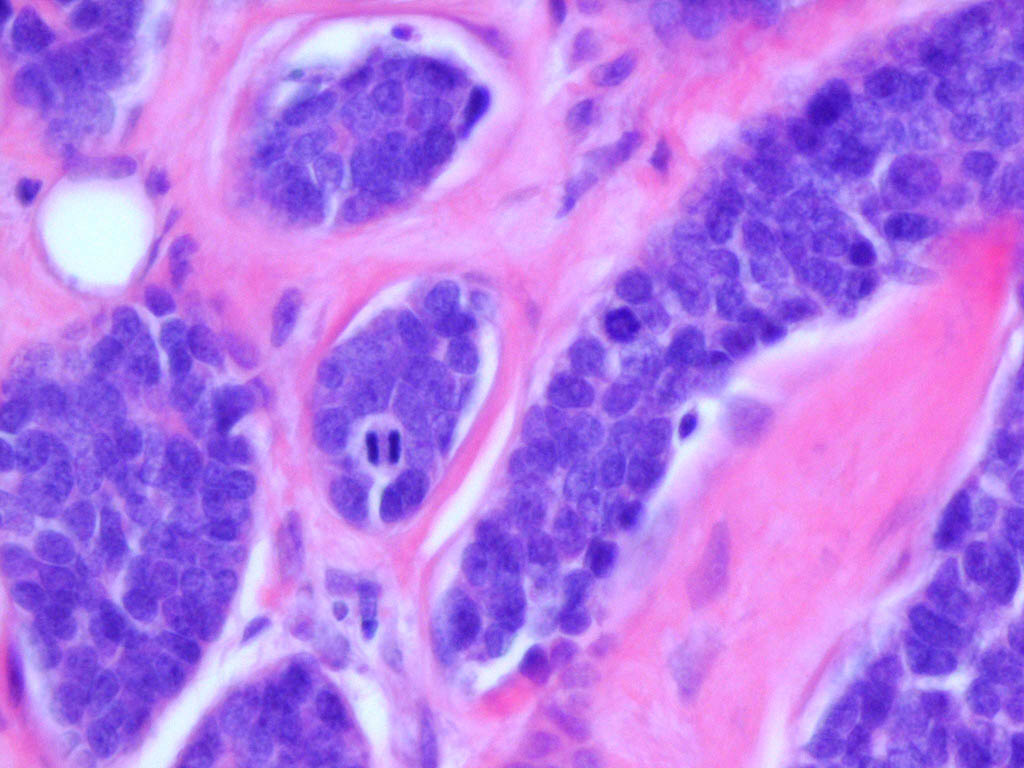

Cylindroma =الأسطوانوم

OLYMPUS DIGITAL CAMERA